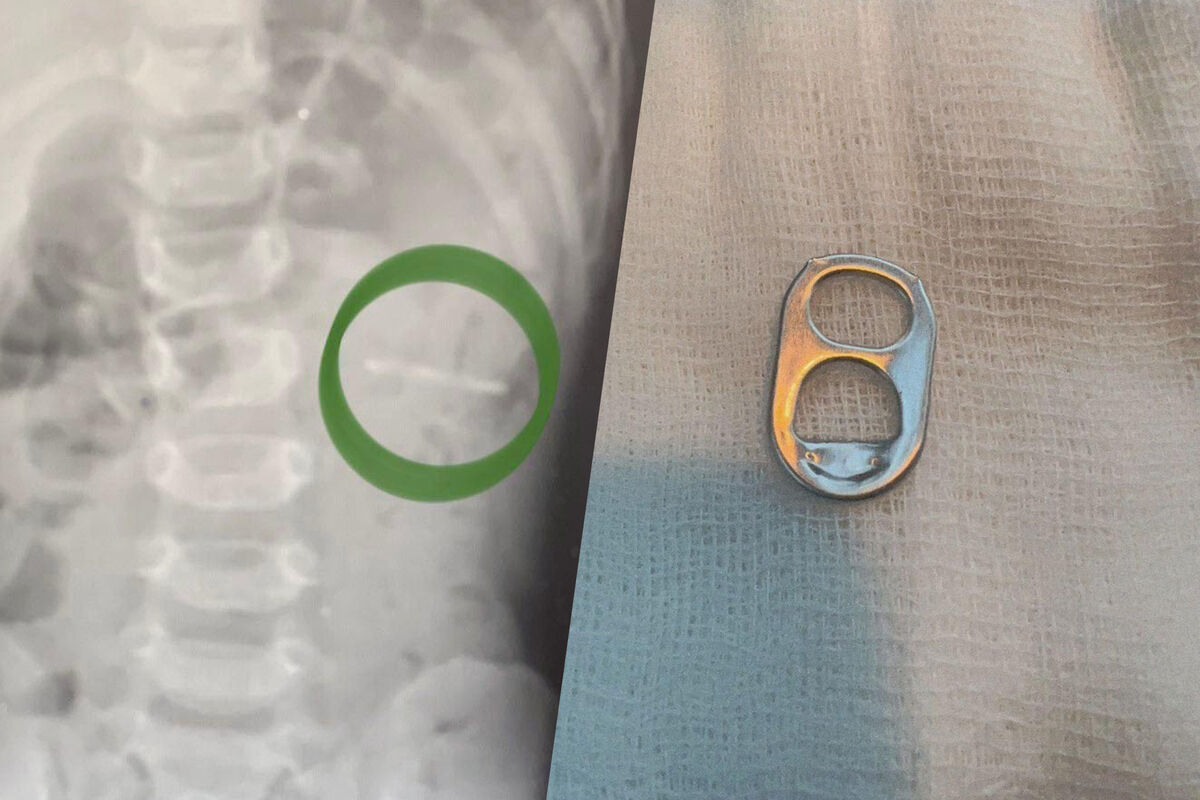

Врачи Раменской больницы спасли полуторагодовалого ребенка, который проглотил ключ от металлической банки. Об этом сообщили в пресс-службе минздрава Московской области.

Мальчика в больницу привезли родители. Они рассказали, что сын играл с маленькой деталью и по неосторожности проглотил ее. Обследование показало, что ключ от банки находится в желудке.

«Слизистые оболочки внутренних органов были не повреждены. При помощи эндоскопического инструмента металлический предмет с острыми краями был аккуратно извлечен», — рассказал заведующий детским хирургическим отделением больницы Владимир Хабалов.